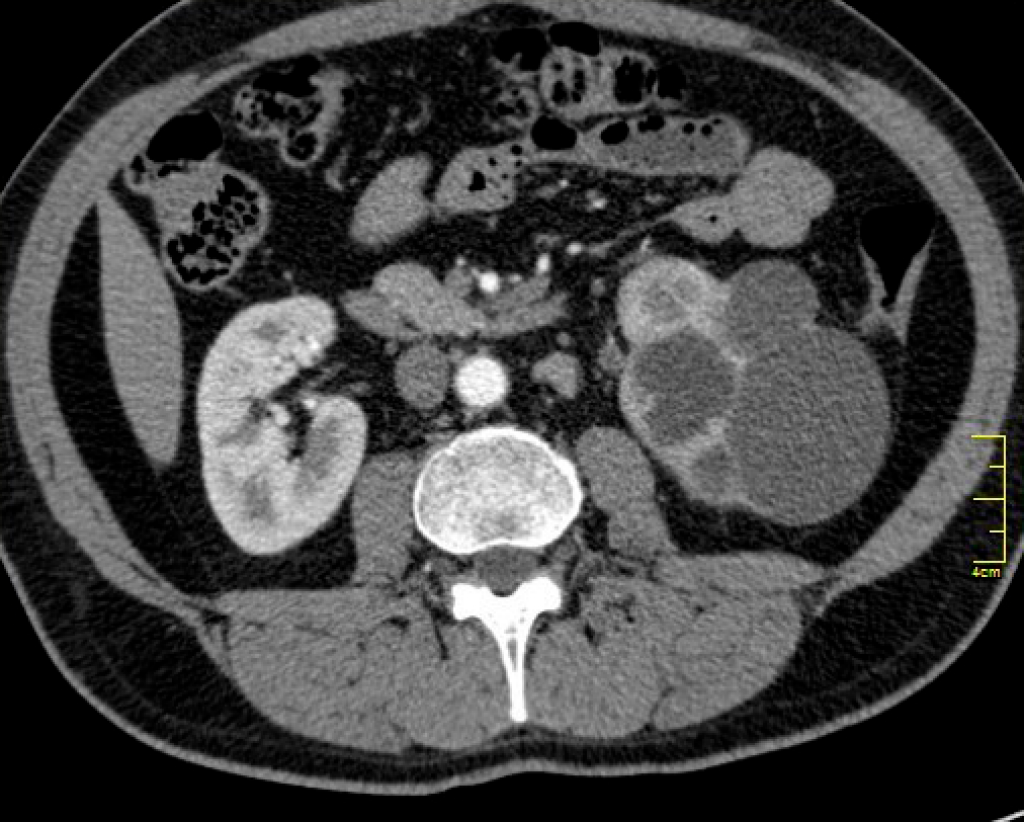

Понимание кавернозного туберкулеза почки

Раздел: Мудрость в деталях